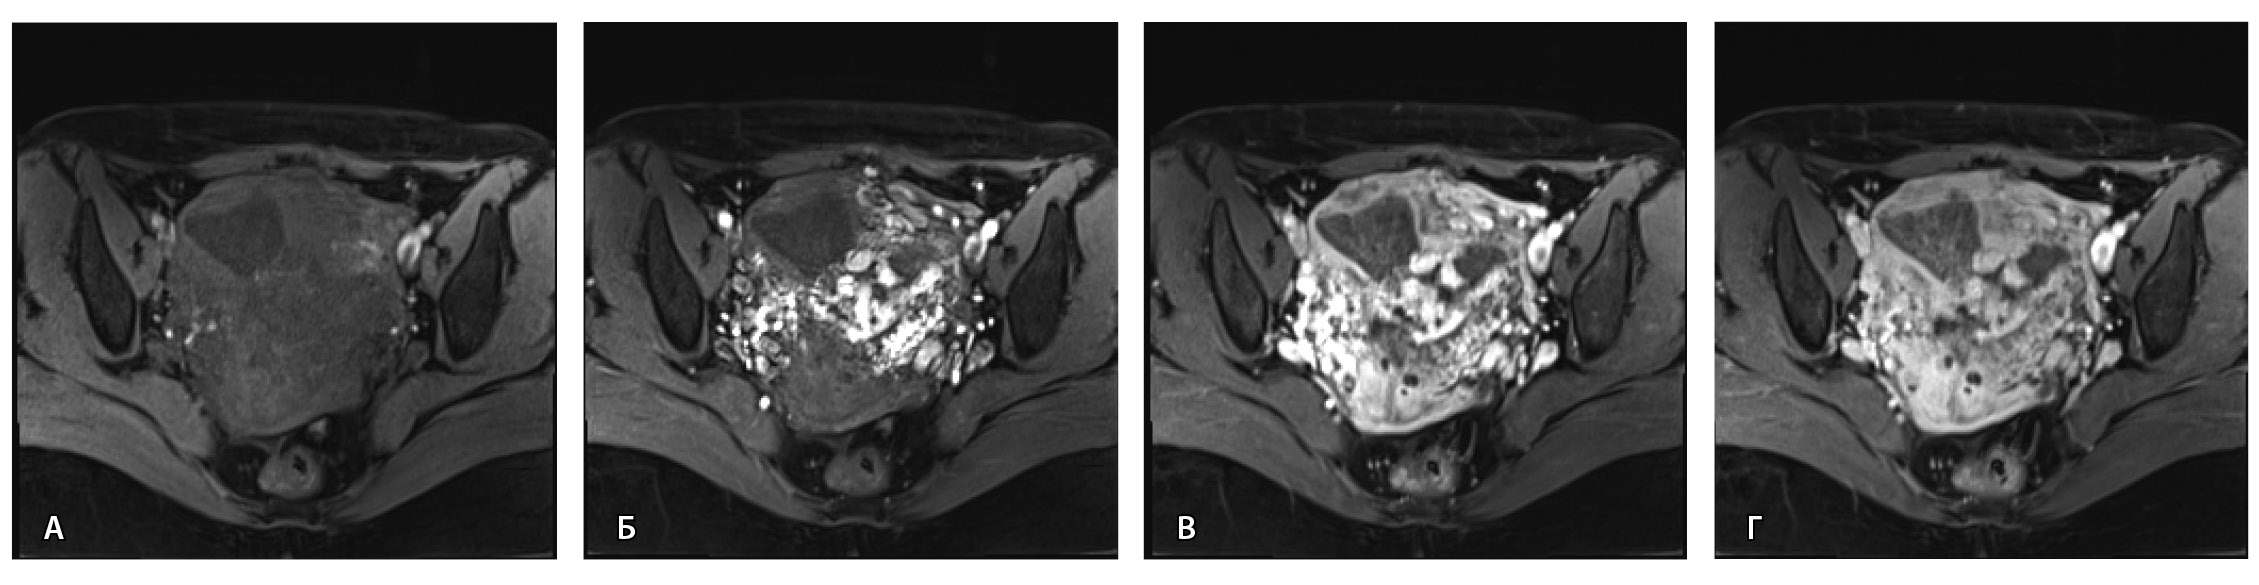

По наружной поверхности нижнего маточного сегмента и в параметрии определяется наличие полнокровной сосудистой сети с артериовенозными анастомозами. При контрастировании визуализируются фрагментарные участки гиперваскулярного накопления контраста вышеописанным образованием в рубцовой нише, а также определяется наличие артериовенозной сосудистой мальформации (рис. 2).

Рис. 2. Магнитно-резонансная томограмма, динамическое контрастное усиление в режиме Т1-взвешенного изображения FS. До контраста (А), в раннюю артериальную фазу (Б), паренхиматозную фазу (В), выделительную фазу (Г) определяются многочисленные патологические сосуды, зоны неоангиогенеза, сосудистые шунты как в стенке матки, так и в параметрии по типу артериовенозной мальформации